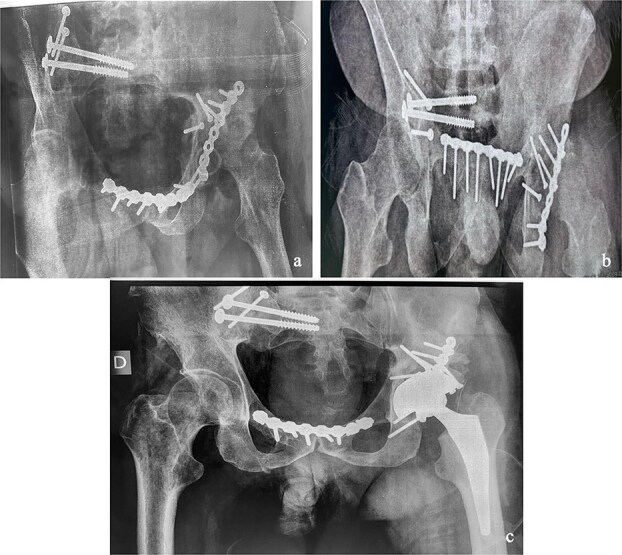

由于手术技术和策略的复杂性,骨盆环和髋臼骨折在不愈合或不愈合的晚期是一个治疗挑战。我们报告一例42岁男性患者骨盆和左髋关节外伤诊断后40天的伤害,经过长期重症监护的严重胸部外伤。影像学显示为Tile-AO B1-2骨盆骨折伴髋臼横后壁骨折和股骨头脱位。采用多路手术切除骨痂,实现复位和固定。最初的结果是有利的。10个月时,患者出现左髋关节骨关节炎并接受了原发性全髋关节置换术。在36个月的随访中,他的哈里斯髋关节评分为85分,马吉德评分为86分,并恢复了接近正常的日常活动。这些复杂的病例需要仔细规划,早期手术复位对于移位的近期骨折至关重要。

Managing pelvic ring and acetabular fractures at a late stage of malunion or nonunion is a therapeutic challenge due to the complexity of both the surgical technique and strategy. We report the case of a 42-year-old male patient with pelvic and left hip trauma diagnosed 40 days postinjury, after a prolonged intensive care stay for severe chest trauma. Imaging revealed a Tile-AO B1-2 pelvic fracture with associated transverse-posterior wall acetabular fracture and femoral head dislocation. A two-stage surgery using multiple approaches was performed to remove callus and achieve reduction and fixation. The initial outcome was favorable. At 10 months, the patient developed left hip osteoarthritis and underwent primary total hip arthroplasty. At 36-month follow-up, he had a Harris Hip Score of 85, a Majeed score of 86, and had resumed near-normal daily activities. These complex cases require careful planning, with early surgical reduction being essential in displaced recent fractures.